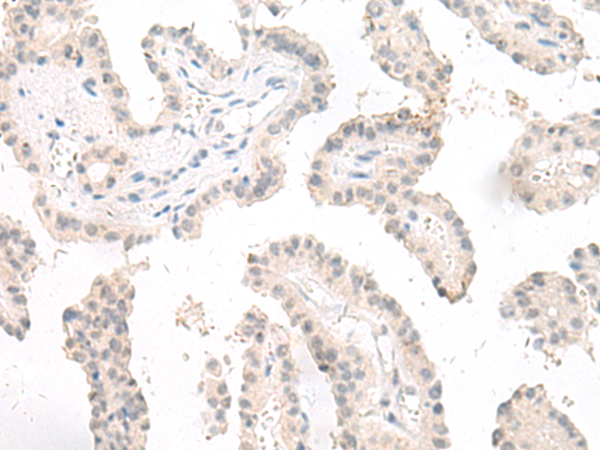

分类: 科研抗体货号: P13460别名: LGP1; D11LGP1应用: IHC反应种属: Human